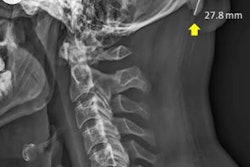

Australian researchers studied x-rays of 1,200 individuals ages 18 to 86, finding that those who were male, younger, and had a higher degree of forward head protraction were more likely to also have enlarged external occipital protuberances at the base of their skulls. The authors speculated that these protuberances developed as a musculoskeletal response to heavy mobile device use as the body compensated for the head's heavier weight in the forward position.